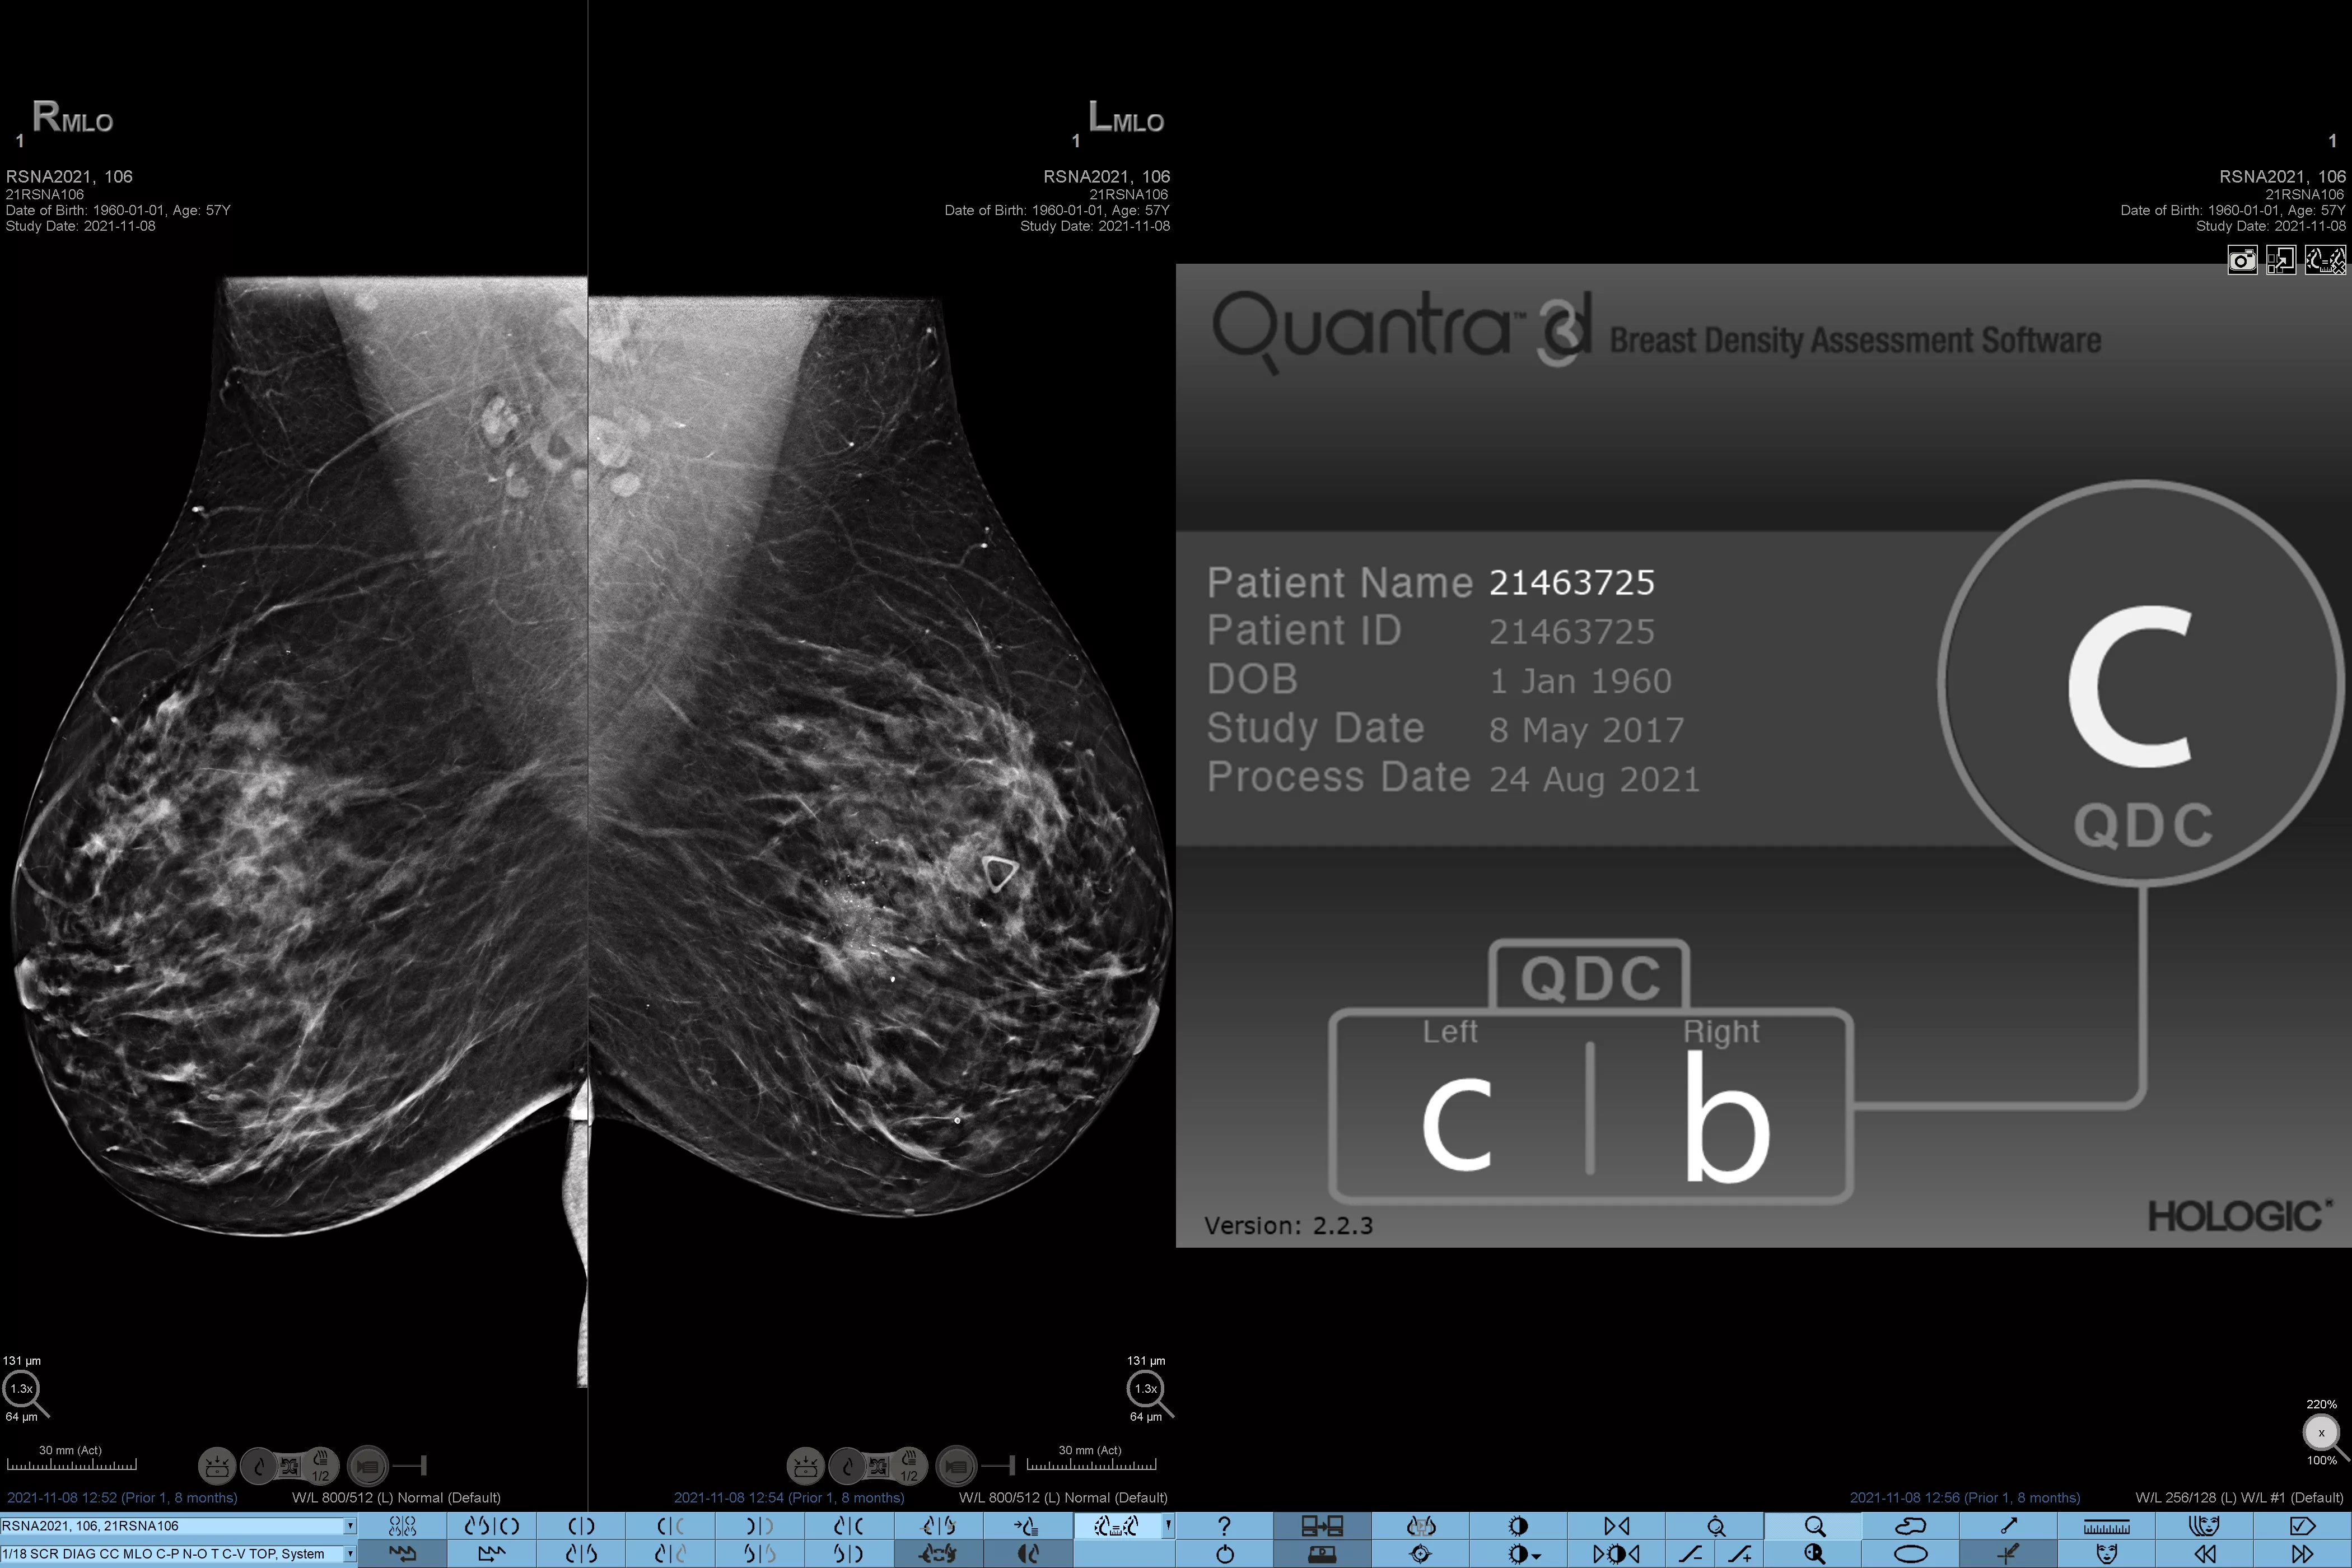

Higher breast density is known to increase a woman’s risk for breast cancer.1 The need for accurate, unbiased analysis is therefore critical. Powered by machine learning, Quantra technology software analyses both 2D™ and tomosynthesis images for distribution and texture of parenchymal tissue. It categorises breasts in four breast composition categories consistent with guidance from the American College of Radiology (ACR) BI-RADS Atlas 5th Edition.2

Objective machine learning algorithm that assigns breast density category based on analysis of breast tissue texture and patterns.

Breast imaging scans